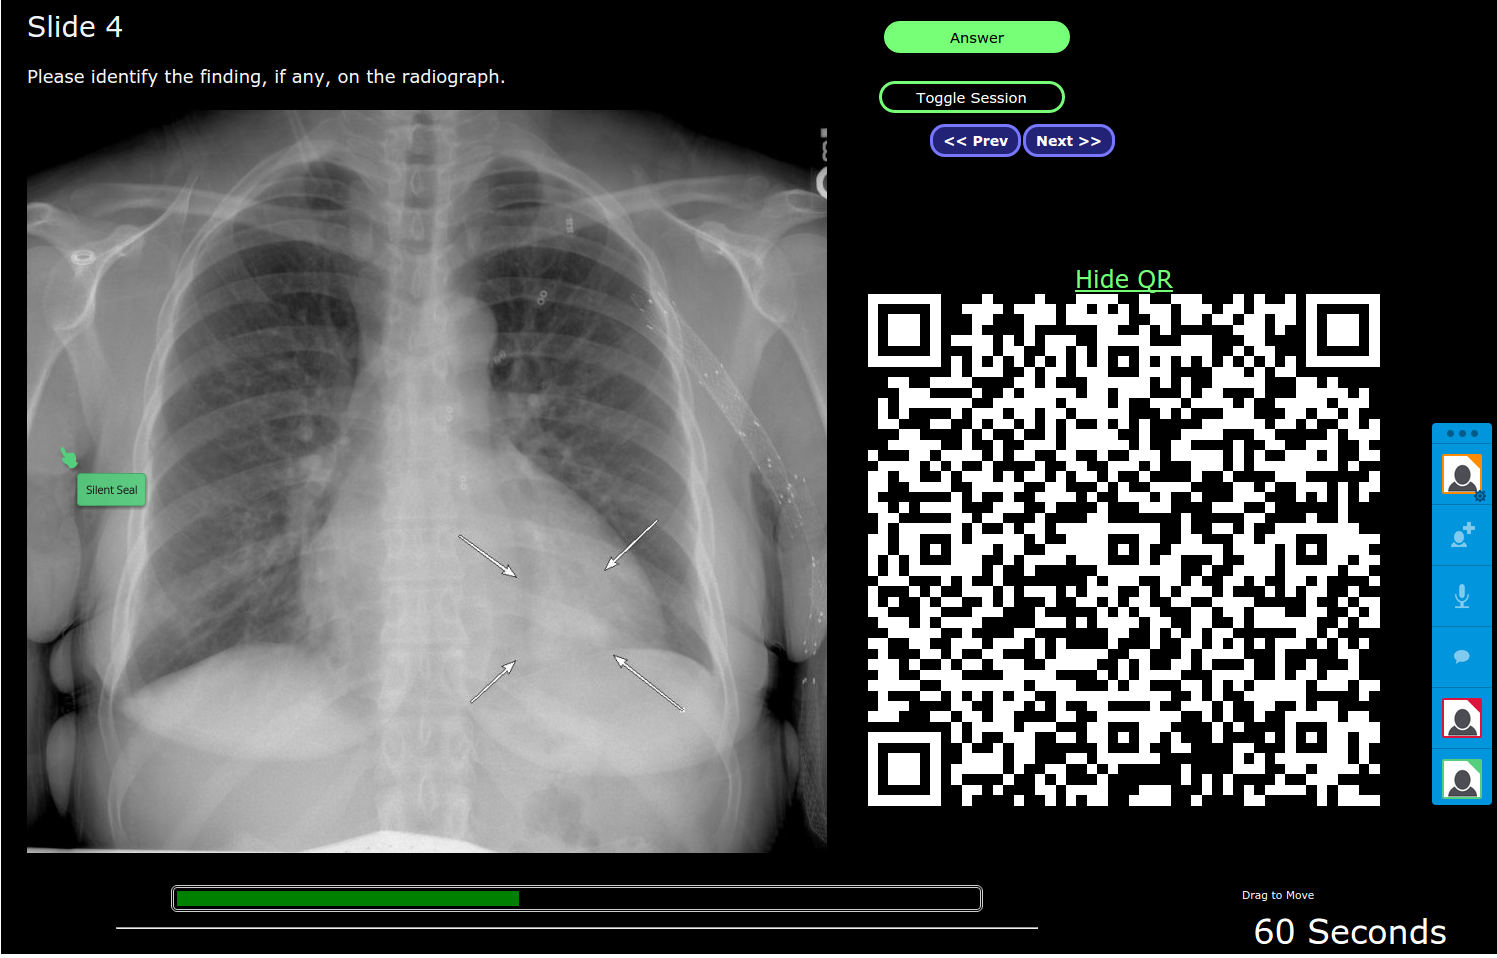

3. A QR code is made available so the audience can use QR scanner on their phone or tablet device to join the discussion. The QR code can be dragged out of the way or hidden.

4. A timer is available so the presenter can "quiz" the audience to log in and point at where the disease is before time runs out.

5. A user can follow along with the speaker (if they are on the same slide together), or review the slides on their own from their mobile device (using the Next/Prev buttons).